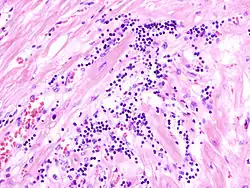

Virale Myokarditis

Mikro: Interstitielles lymphozytäres Infiltrat (kleine blaue Zellen), kaum Nekrosen.

Virale Myokarditis bei Patient mit plötzlichem kongestiven Herzversagen, Autopsiepräparat, H&E.

idem.